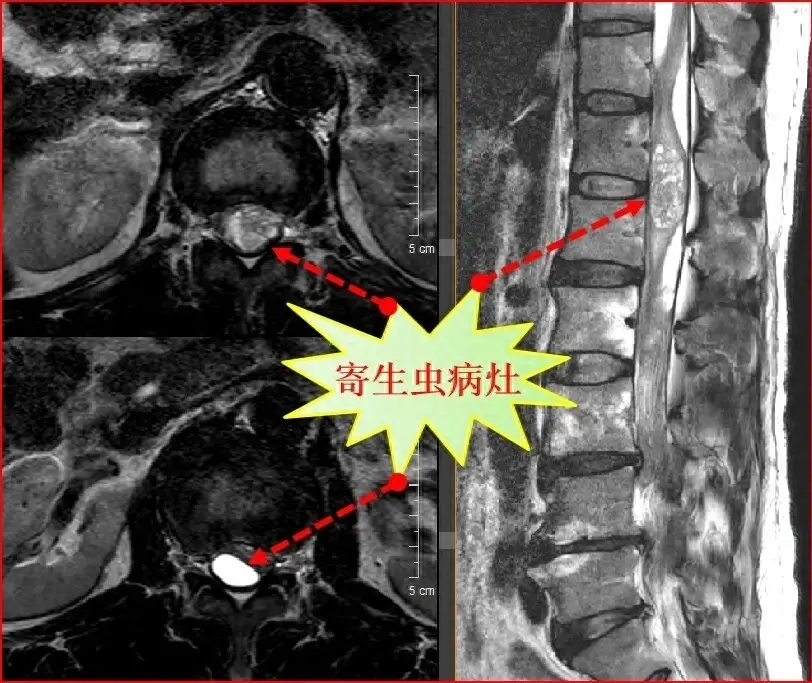

然而,不幸的是,最近他開始出現了一系列病癥,包括嚴重的胃痛、惡心和嘔吐,同時他的肌肉也變得僵硬無力。經過多次檢查和專家的診斷,驚人的結果讓人震驚:這位男子的身體出現了嚴重的中毒癥狀,導致其器官功能受損。